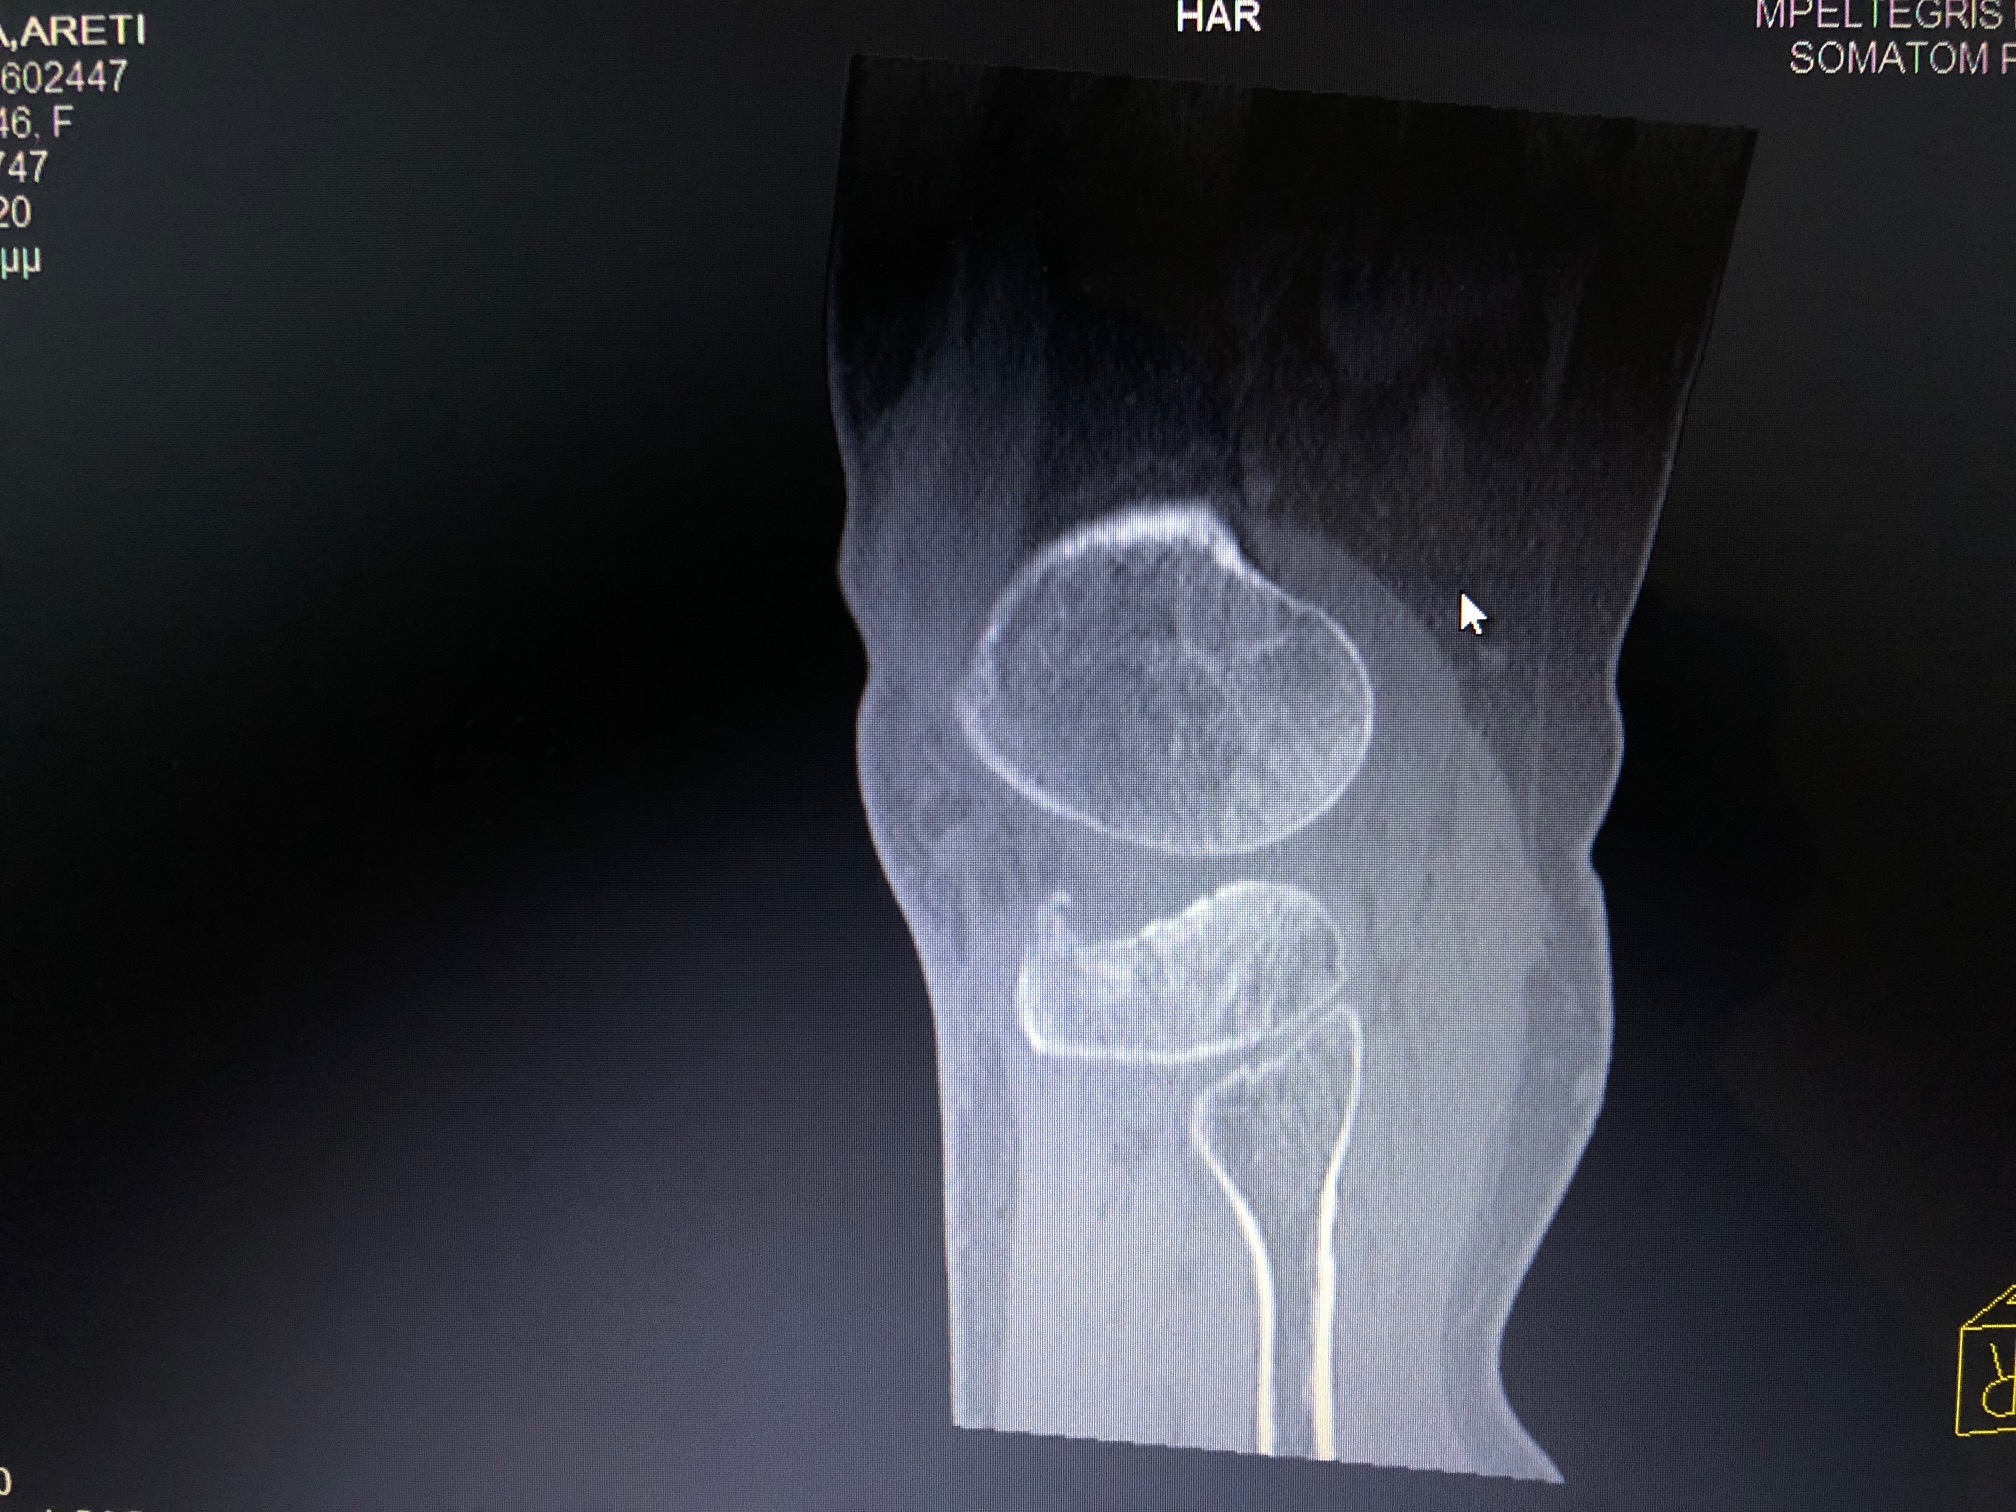

Η διάγνωση ενός κατάγματος κνημιαίου plateau πραγματοποιείται από έναν έμπειρο Ορθοπαιδικό. Αρχικά η λήψη ενός λεπτομερούς ιστορικού και η κλινική εξέταση του ασθενούς είναι απαραίτητα. Στην συνέχεια για την διάγνωση αλλά και την ταξινόμηση του κατάγματος είναι υποχρεωτική η διενέργεια ακτινολογικού ελέγχου. Ο έλεγχος αυτός περιλαμβάνει απλές ακτινογραφίες (φας, προφιλ και λοξές) ενώ πολλές φορές απαιτείται περαιτέρω διερεύνηση με αξονική τομογραφία για την πλήρη κατανόηση της μορφής του κατάγματος και τον σωστό προεγχειρητικό σχεδιασμό.